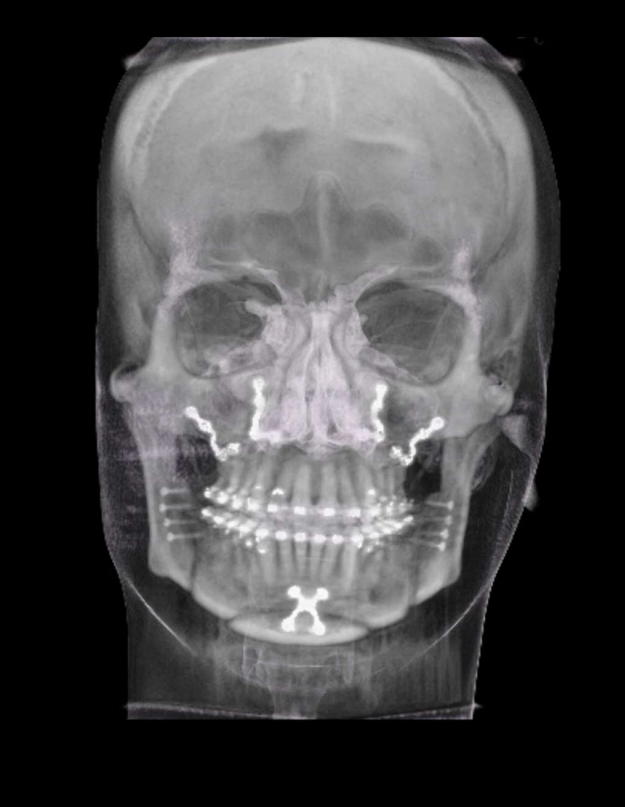

TC de face (do Hióide à Glabela), reconstrução 3D do tecido ósseo, radiografia panorâmica, telerradiografia lateral e frontal com traçado, cortes transversais e axial de maxila/mandíbula e arquivo DICOM – entregue em pasta de Pvc.

TC de face (do Hióide à Glabela), reconstruções 3D do tecido mole/ósseo/vias aéreas, radiografia panorâmica, telerradiografia lateral e frontal com traçado, cortes transversais e axial de maxila/mandíbula, ATM e arquivo DICOM – entregue em pasta e caixa de Pvc.